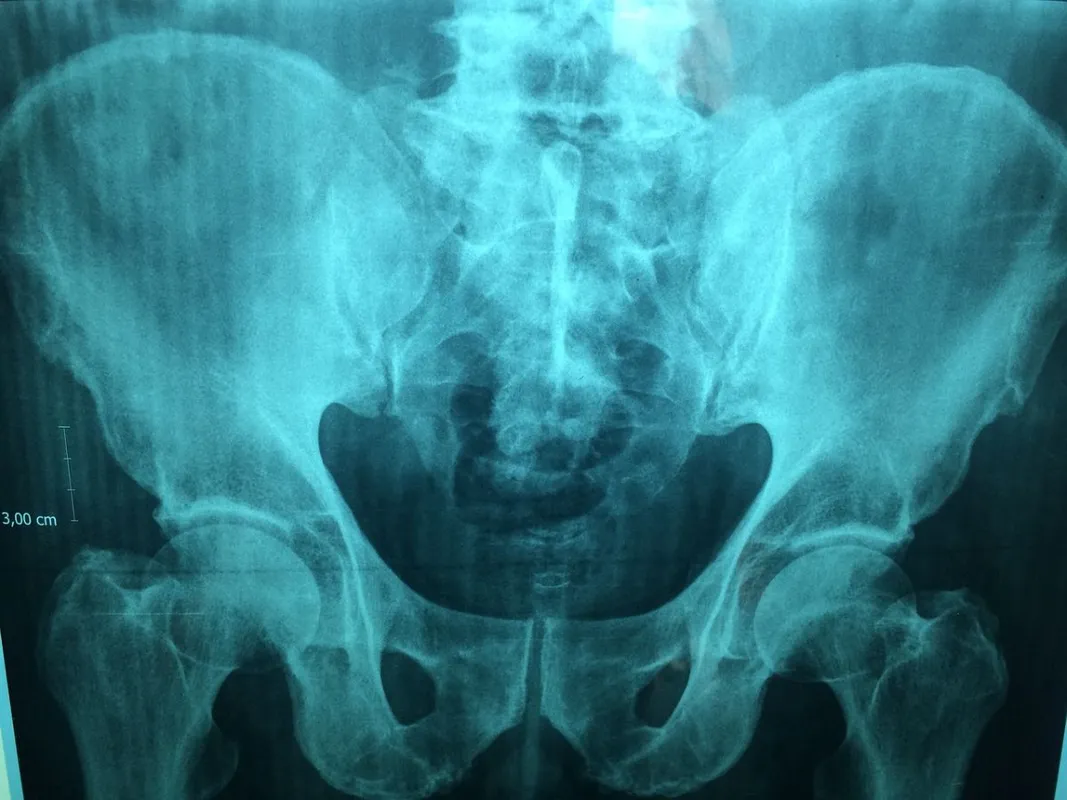

A röntgenfelvétel kimutatta, hogy egészen a húgyhólyagjába sikerült felnyomnia, így mindenképpen műteni kellett. Egy bemetszésen keresztül sikerült biztonságosan eltávolítani a hőmérőt. Arról azonban nem adtak tájékoztatást, hogy a fiú maradandó sérüléseket szenvedett-e.